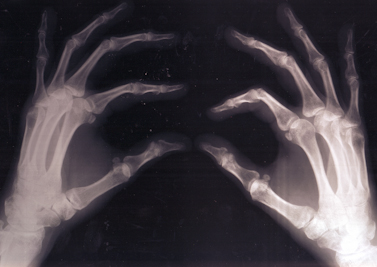

Will recent advances in human tissue preservation change the way we think about bodies, death, God… and China?